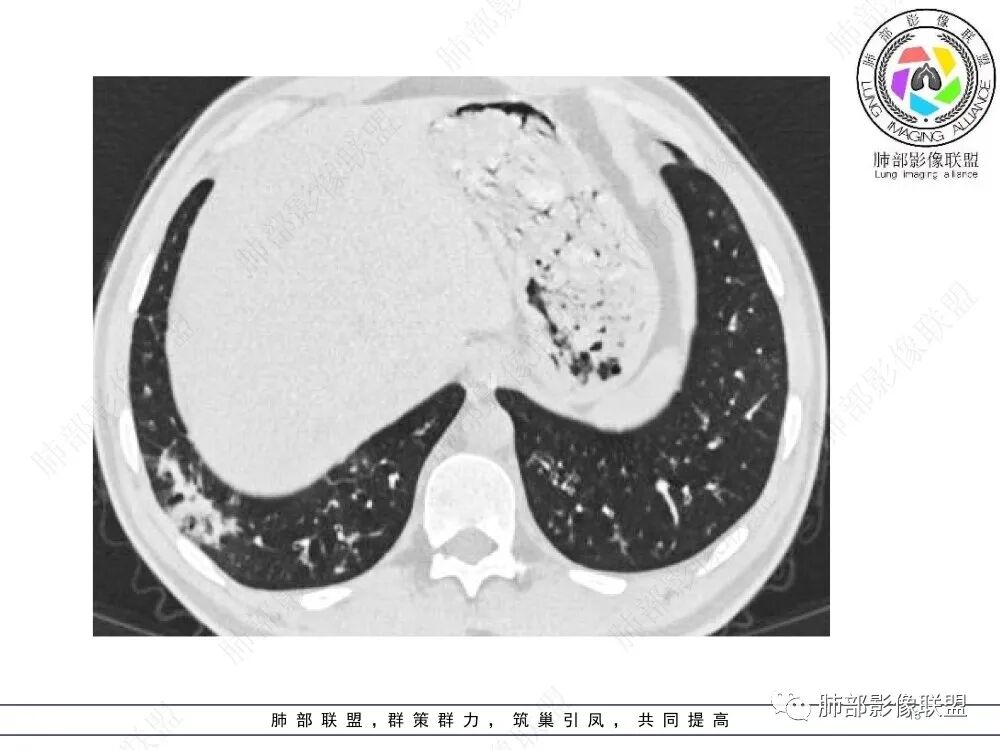

肺部影像联盟晨读病例肺气肿,多发气管壁增厚,片状影,符合气道分布,考虑气道侵袭性曲霉菌病。

中年男性,慢性咳嗽,有吸烟史,胸部CT基础尚可,双肺多发的沿支气管播散的树芽影以及支气管管壁的增厚和对应区域内的斑片影实变影,符合气道播散的表现。经过对症抗感染治疗1月之后,胸部CT影像进展。右侧播散到左侧。实变和漱牙以及气管壁增厚均较前明显进展。

2.胸部CT:两肺广泛的支扩,支气管壁增厚,多发的树芽影,部分伴有支气管周围的渗出,少量实变。不足一月复查,原有支扩、支气管壁增厚基础上伴有大量渗出,实变,结节,胸膜下累及。

3.综合分析:首先病灶沿支气管分布,呈树芽征及实变影,相应支气管壁广泛增厚,其次病变范围比较广泛,几乎累及所有叶段,这种表现常高度提示气道播散,经过对症抗感染治疗20多天后,胸部CT影像明显进展。符合IPA的进展表现。